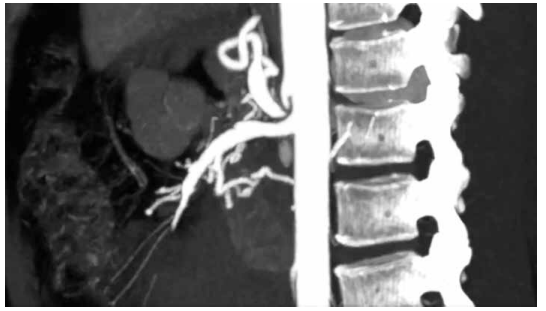

Paciente de 42 anos sofreu laceração profunda no antebraço direito por vidro, com secção completa da artéria radial. O teste de Allen demonstra preenchimento palmar adequado pela artéria ulnar em menos de cinco segundos.

Considerando o quadro apresentado, qual é a conduta mais adequada em relação à lesão arterial?